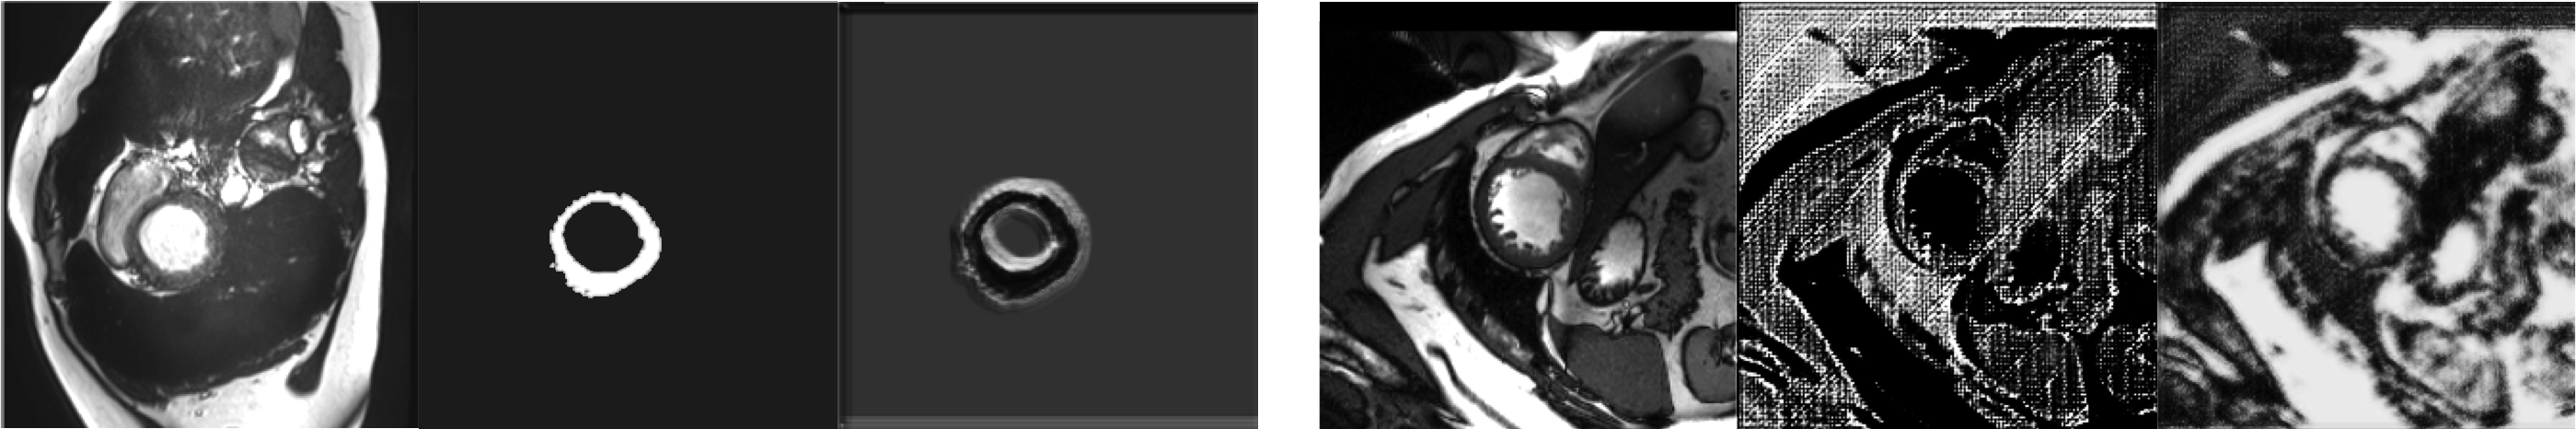

3 Proposed Approach: the SDNet

Motivation: A useful latent representation is one that describes the data well. Spatial (segmentation) maps can be considered a form of latent variable that allows visual inspection of what a network learns. At the same time, an easy (unsupervised) way to see whether a latent representation captures the data is to use a decoder to reconstruct the input. In fact, even CycleGANs are autoencoders: they encode (and decode) the input via an intermediate output and thus inspire the design of our approach. Yet they have problems particularly when the intermediate output is discretised (a binary mask) and supervised losses are introduced. Their performance heavily depends on the weighting of the losses, as shown in Fig. 1. If the segmentation loss is weighted higher than the reconstruction loss, it is not possible to reconstruct the input since the binary mask does not contain enough information for the transformation. When differently weighted, information is stored in the binary mask ruining semantics. This confirms findings of others, that a CycleGAN resolves the many-to-one/one-to-many problem by storing low-frequency information in the output image [8]. We can see that the two losses are antagonistic, and a standard CycleGAN is not suitable as is. We need to introduce variables that break the many-to-one problem, encouraging a balance between the losses to achieve good segmentation and reconstruction.